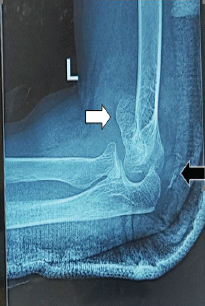

Capitellum Fracture with Distal Triceps Tendon Avulsion Injury: A Rare Presentation with Literature Review

Rajdeep Das , Sharan Mallya , Ashok Puranik , Rahul Kar

………………………………p.88-94